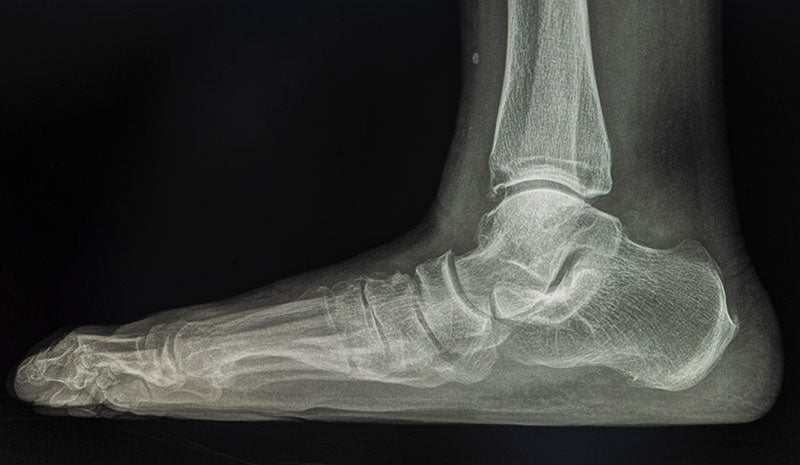

Feet that seem to have no arches and make contact with the ground at nearly every point across the bottom are known as flat feet. This is often a result of a loss of arch, sometimes called a collapsed arch, which is formed by tension in tendons of the foot, though sometimes it can be a result of anatomical differences at birth. Whatever the cause of the condition, having flat feet can be difficult and painful.

People with flat feet report a range of symptoms from having no pain at all to experiencing pain in their heels, ankles, knees, back, or even hips. Flat feet have also been associated with symptoms like bunions and hammer toes. This makes sense if you think about how shoes are generally constructed for people with normal arches. Wearing ill-fitting shoes can cause bunions and hammer toes and people with flat feet might have a difficult time finding shoes that fit well. And as flat feet are a result of loss of arch which helps to keep the foot in an upright and stable position, it causes the ankles to leave their neutral position and roll inward. This can affect the alignment of your body from your ankles all the way up your spine to your neck.